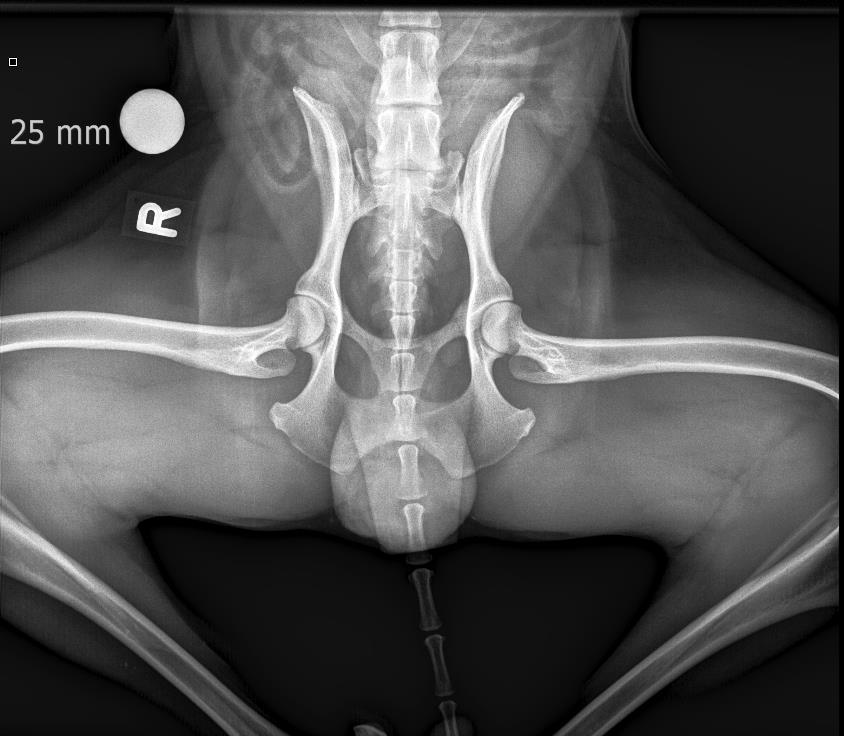

• HD Abklärungen

• ED Abklärungen

HD und ED Beurteilungen werden nach Wunsch des Besitzers oder nach Vorgaben der Rasseklubs jeweils von der HD-Kommission in Zürich oder Bern beurteilt. Für unsere deutschen Kunden ist auch ein Versand nach Deutschland möglich